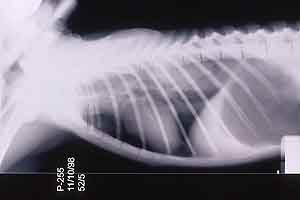

- Case 23-3. The A/P thoracic radiograph shows marked

right sided deviation of the cardiac silouette. The lateral thoracic

radiograph shows diffuse fluid density in dorsal lung fields.

- Thoracic radiographs demonstrated an increased pulmonary

interstitial pattern with air bronchograms bilaterally. The cardiac

silhouette was shifted to the right. Abdominal radiographs demonstrated

hepatomegaly and the presence of excessive gas in the stomach,

small intestine, and colon. Supportive treatment, including oral,

subcutaneous, and intravenous fluids, antibiotics, and vitamins

were administered, but response to treatment was minimal and

the monkey was euthanized in late 1998.